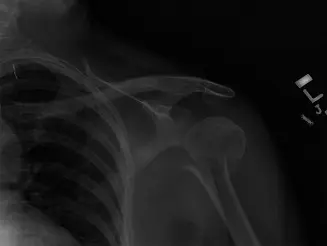

- الأشعة السينية (X-rays): هي الفحص الأولي والأكثر أهمية لتشخيص كسر عظم العضد. تُؤخذ صور متعددة من زوايا مختلفة (عادةً منظران أمامي جانبي ومائل) لتحديد موقع الكسر، نمطه (مستعرض، مائل، حلزوني، مفتت)، مدى تبدل العظم، ووجود أي شظايا عظمية.